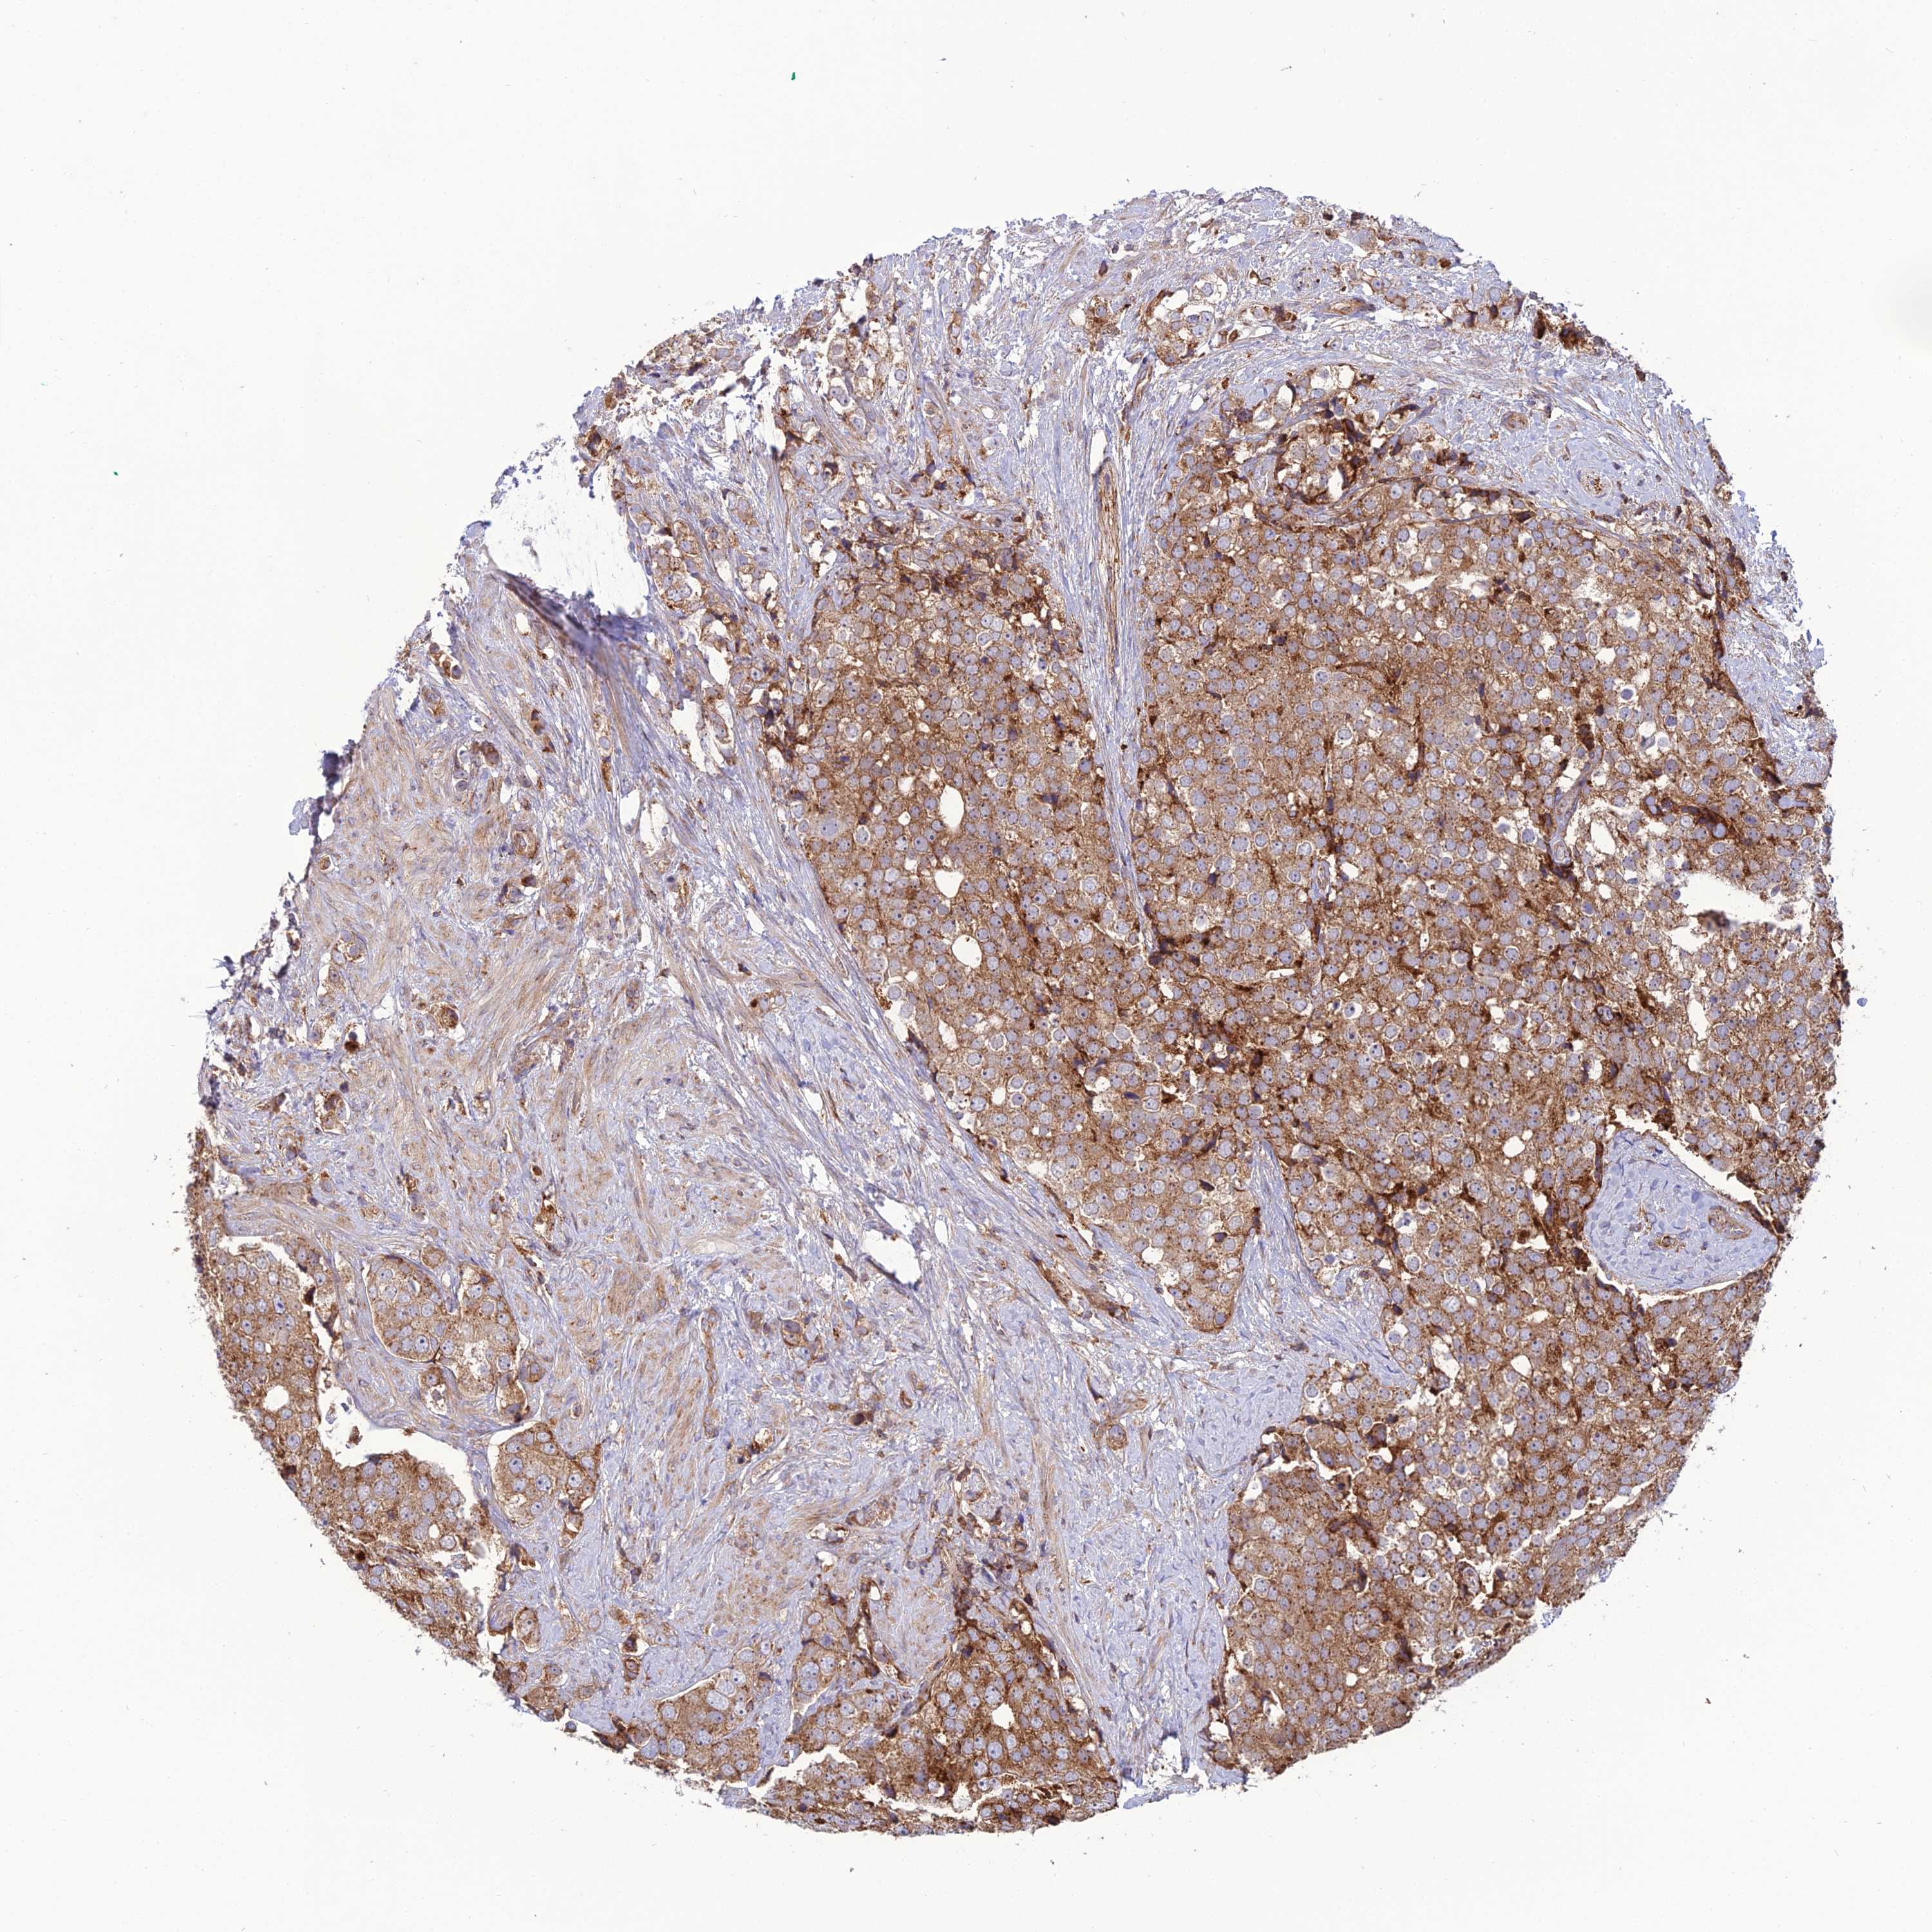

PROSTATE CANCER - Protein expressioni

A mouse-over function shows sample information and annotation data. Click on an image to view it in a full screen mode. Samples can be filtered based on level of antibody staining by selecting one or several of the following categories: high, medium, low and not detected. The assay and annotation is described here.

Antibody stainingi

Antibody staining in the annotated cell types in the current human tissue is reported as not detected, low, medium, or high, based on conventional immunohistochemistry profiling in selected tissues. This score is based on the combination of the staining intensity and fraction of stained cells.

Each image is clickable and will lead to virtual microscopy that enables deeper exploration of all samples and also displays staining intensity scores, fraction scores and subcellular localization as well as patient and tissue information for each sample.

Antibody HPA043642

Staining

High

Medium

Low

Not detected

Intensity

Strong

Moderate

Weak

Negative

Quantity

>75%

75%-25%

<25%

None

Location

Nuclear

Cytoplasmic/membranous

Cytoplasmic/membranous,nuclear

Adenocarcinoma, NOS

Adenocarcinoma, High grade

Adenocarcinoma, Low grade